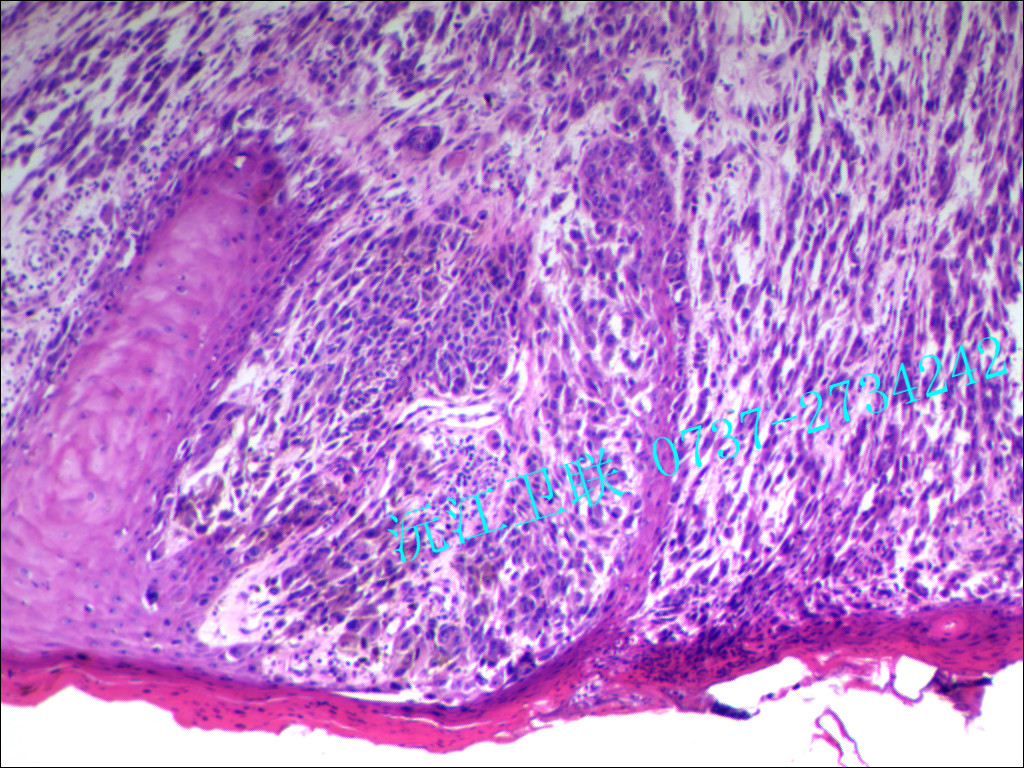

我們的主要產(chǎn)品有:病原微生物學(xué)、免疫學(xué)、寄生蟲(chóng)學(xué)、病理學(xué)、組織學(xué)、口腔學(xué)、血液檢驗(yàn)學(xué)、生物遺傳學(xué)、藥用植物學(xué)、動(dòng)物學(xué)、植物學(xué)切片(裝片)標(biāo)本。寄生蟲(chóng)學(xué)、病理學(xué)、組織胚胎學(xué)浸制標(biāo)本。解剖陳列標(biāo)本、解剖模型共計(jì)品種有五千余種。